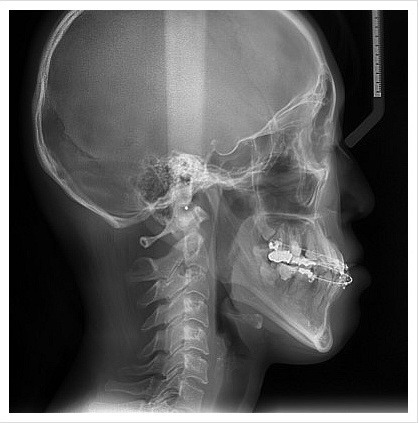

양악수술은 여러 단계로 이루어집니다. 먼저, 환자의 상태를 진단하기 위해 X-ray 촬영과 3D 스캔을 진행합니다. 이후, 수술 계획을 세우고, 수술 당일에는 전신 마취를 시행합니다. 수술 과정은 상악과 하악의 뼈를 절단하고, 필요한 위치로 이동시킨 후 고정하는 방식으로 진행됩니다. 수술 시간은 보통 1~7시간 정도 소요됩니다.

| 양악수술전(옆면) | 양악수술후(옆면) |